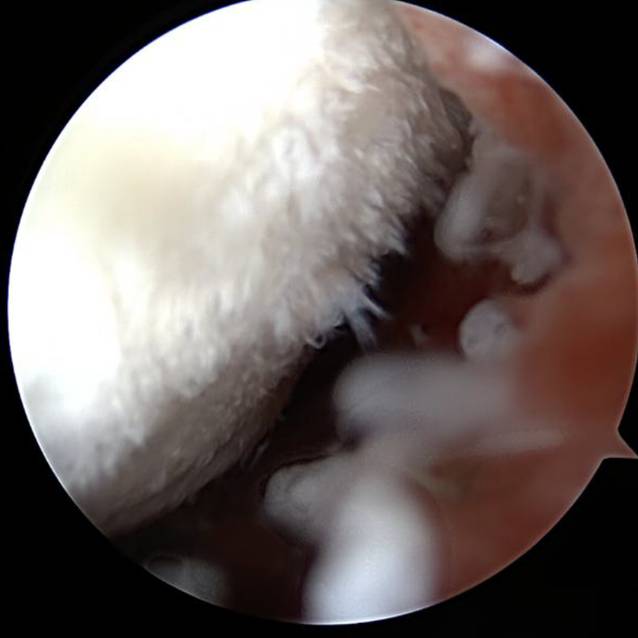

Abb. 5

Mini-open Schulter links: Entfernung des superioren DogBone-Buttons

Intraoperativ stellt sich eine ausgeprägte Synovialitis mit serösem Erguss und deutlichen Verklebungen dar. Es erfolgte eine Synovektomie und Bursektomie der Bursa subcoracoidea sowie die Entfernung multipler Knorpelfragmente (Abb. 3). Nach weiterer Präparation des Korakoids und des subkorakoidalen Raums war die Bergung des frei florierenden inferioren DogBone-Buttons ventral der Subskapularissehne möglich (Abb. 4). Anschließend konnten die Fäden und der superiore DogBone-Button mini-open dargestellt und ebenfalls geborgen werden (Abb. 5).